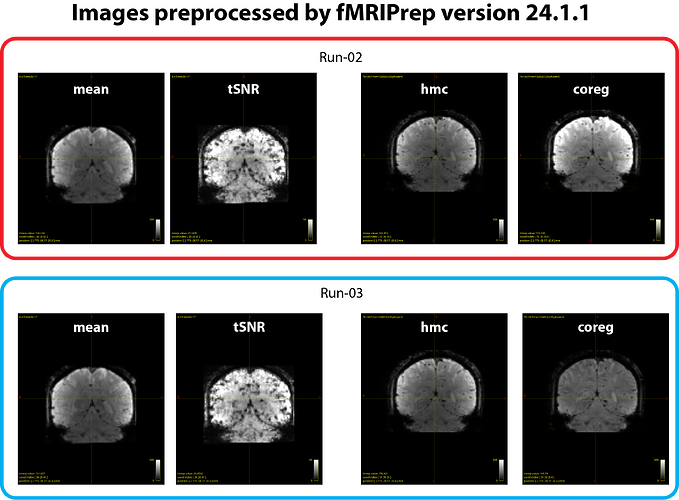

The issue is that the image intensity of the *_desc-coreg_boldref.nii.gz files is inconsistent across runs. As we understand, this image is used for coregistration to the T1-weighted image, and a bias-field correction is typically applied to improve alignment. However, this correction seems to succeed in some runs (e.g. run-03 in our case) but not others (e.g. run-02 in our case), resulting in marked intensity differences across runs. We have attached example images illustrating the issue (see figure 2 below). This phenomenon occurred with fMRIPrep v24.1.1, and runs showing this inconsistency also yield weaker or absent BOLD z-score signals in the GLM results.

- tSNR maps look similar across runs (see figure 1 and 2).

*_desc-hmc_boldref.nii.gzimages (generated just before the coregistration step) are also consistent (see figure 2).

Thus, the inconsistency seems to arise at the *_desc-coreg_boldref.nii.gz step.